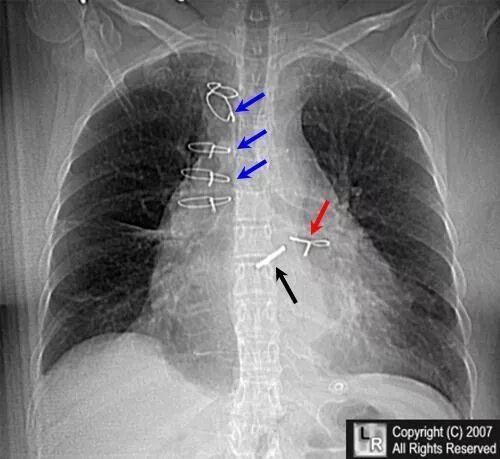

Медиастинит причины